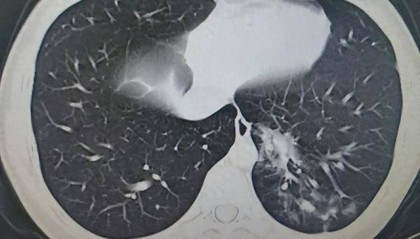

美博主印度卧铺旅行15小时后,因呼吸道严重感染入院治疗

【环球时报特约记者 白元】《印度快报》4日报道称,美国旅行博主尼克·马多克在印度火车旅行期间,因呼吸...